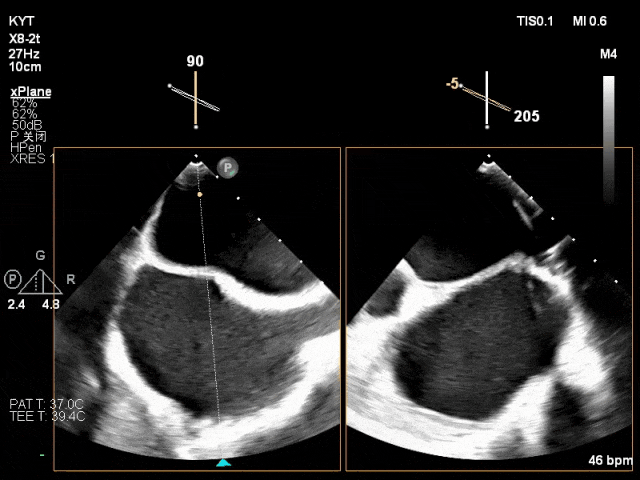

超声心动:二尖瓣脱垂(PC区)合并腱索断裂,二尖瓣反流(重度,4+级,Carpentier II),左房增大,主动脉瓣狭窄(轻度),三尖瓣反流(轻度)。

1.患者为PC区“大舌头样”脱垂,后叶短小长度仅有4-5mm,脱垂范围较宽,分型为Carpentier II 型,但同时也存在心脏扩大对引起的后叶栓系所致二尖瓣对合不良,考虑为DMR+FMR;

2.结合患者二尖瓣内交界宽大脱垂、后叶较短的解剖特征,拟采用第一枚夹子首先钳夹前叶和交界组织,再于靠近中央区放置第二枚夹子以提供更加稳定的夹持作用。